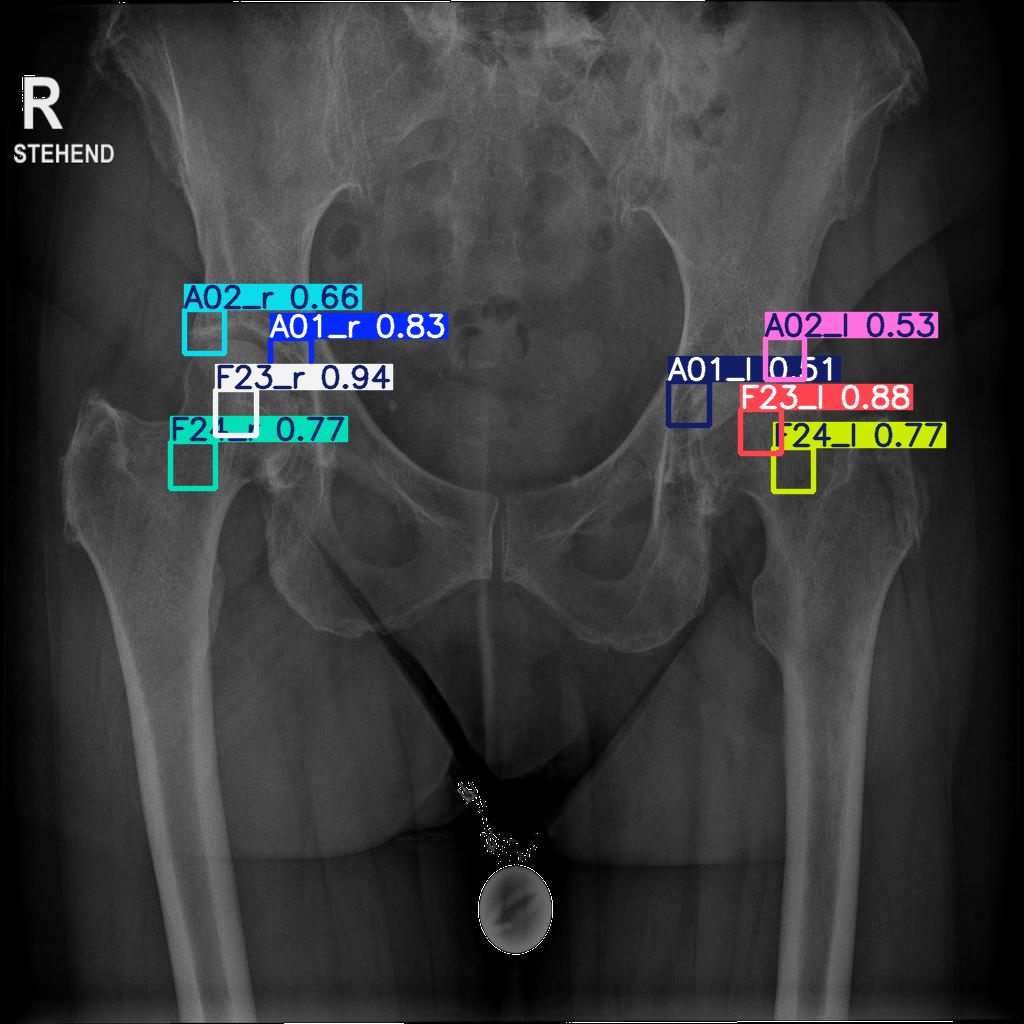

Refer to caption

Figure 2: uNet prediction errors (mm) for the test individuals. A01 acetabulum medial sourcil, A02 acetabular lateral sourcil, F23 centre of hip rotation, F24 femoral neck midpoint: _r and _l signifies right and left side accordingly.

The resultant mean and median error values (Tab. 1) are comparable with previous publication by Pei et al.[9].

Predicted bounding boxes were used to find the coordinates of their centres. Interpreted as landmark locations, they were transformed to the original image dimensions. Error point-to-point distances to the ground truth were calculated in mm (Fig. 6). The median errors are within the acceptable range for medical image analysis (3 mm).

The accuracy and precision of labels, predicted by trained pipelines on an unseen test sample, were set as the primary benchmark for the training success. In this respect, the results can be compared with previous publications on automatic landmark identification. For example, Pei et al. [9] reported results for pelvic radiographs. These authors, like the present study, collected eight landmarks from 524 images in an open-source project supported by the Foundation for the National Institute of Health (https://www.niams). nih.gov/grants-funding/funded-research/osteoarthritis- initiative). YOLO detection in the current study (Fig. 6) outperformed both, the uNet that was trained on the same data as YOLO here (Fig. 2), and all the models tested by Pei et al. [9] (Tab. 2).